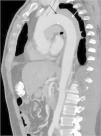

Las DA se pueden clasificar según el sitio anatómico que involucren, de acuerdo con las clasificaciones de Stanford y De Bakey. La clasificación de Stanford divide las disecciones en tipoA si involucra a la aorta ascendente, y en tipoB si involucra a la aorta descendente distal a la emergencia de la arteria subclavia izquierda (fig. 2). La clasificación de De Bakey divide las disecciones en tipo1 si afecta a aorta ascendente, descendente y abdominal, tipo2 si solamente afecta a aorta ascendente, y en tipo3 si afecta solamente a aorta descendente y abdominal.

De acuerdo con la clasificación de Stanford, en nuestro estudio observamos que 17 pacientes (53.1%) fueron catalogados como StanfordA (fig. 4), mientras que los restantes 15 pacientes (46.9%) fueron catalogados como StanfordB (fig. 5). De acuerdo con la literatura, el subtipo StanfordA ocurre en el 60-70% de los casos6. En cuanto a la clasificación de De Bakey, el subtipo3 fue el más frecuentemente diagnosticado, con 15 pacientes (46.9%), seguido del subtipo1, que fue diagnosticado en 10 pacientes (31.2%), y del subtipo2 en 7 pacientes (21.9%).